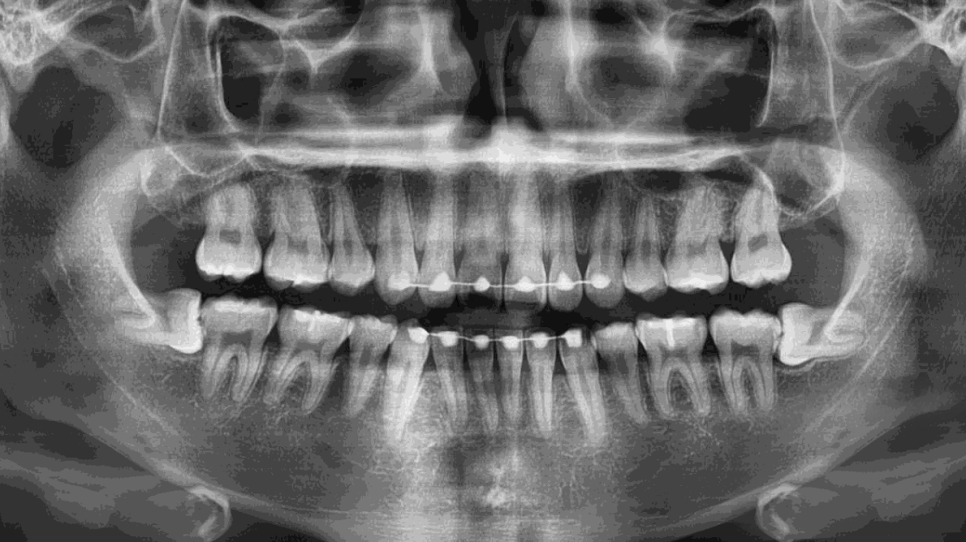

이번엔 대학진학을 앞 둔 10대 후반의 증례!

교정이 끝나서 치열이 매우 가지런해서 보기 좋군요^^

집 근처에서 위쪽 두개는 이미 뽑은 것처럼 보여요.

그러나 아래쪽은..

보다시피 완전히 수평으로

누워있기 때문에 난이도가 높았고,

전문 의료기관을 찾을 필요가 있었던 거죠.

상악 사랑니 두개를 뽑아준 원장님이

하악은 강남레옹치과에 가서

마저 발치를 하라며 권유를 받으셨더라구요.

완전히 누워있기에 저작기능은 전혀 못하는 상황에

오히려 옆 치아에 충치를 일으킬 가능성이

현저해보여 최대한 빨리 뽑는 방향을 말씀드렸습니다.

양쪽을 당일에 한번에 뽑는 건 어렵습니다.

왜냐면 식사를 할 수 없기 때문이죠^^;;

그러나 둘다 얼른 뽑고 싶어 하셔서

2주 간격을 두고 양쪽 사랑니를 모두 발치 완료!!!